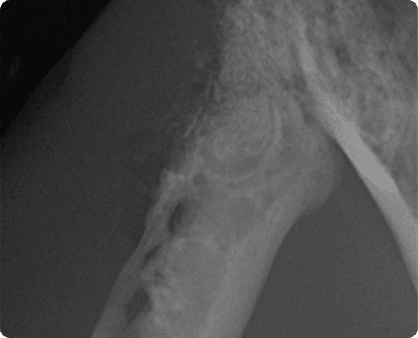

치태, 치석 등에 존재하는 구강 세균에 대한

면역 반응으로 고양이 구강에서 심한 구내염이 발생하거나,

치아가 흡수되어 파괴되는 심한 소모성 질환